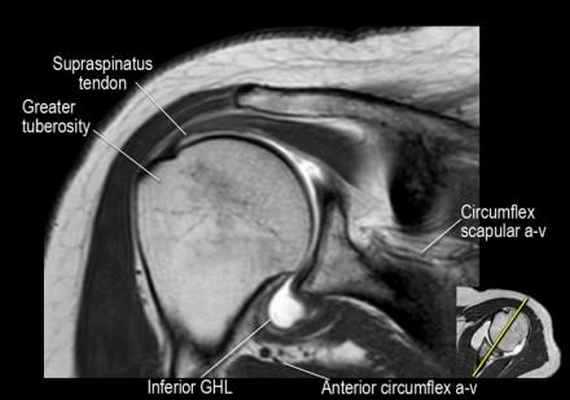

Изображение передних отделов плечевого сустава.

Сухожилие подлопаточной мышцы прикрепляется как к малому бугорку, так и к большому бугорку, давая поддержку длинной головке двуглавой мышцы в борозде двуглавой мышцы. Вывих длинной головки двуглавой мышцы плеча неизбежно приведет к разрыву части подлопаточной сухожилия. Манжета вращателей плеча состоит из сухожилий подлопаточной, надостной, подостная и малой круглой мышц.

Изображение задних отделов плечевого сустава.

Отображены надостная, подостная и малая круглая мышцы и их сухожилия. Все они прикрепляются к большому бугорку плечевой кости. Сухожилия и мышцы манжеты вращателей участвуют в стабилизации плечевого сустава во время движения. Без манжеты вращателей головка плечевой кости частично сместилась бы из суставной впадины, уменьшив силу отведения дельтовидной мышцы (мышцы вращательной манжеты координирует усилия дельтовидной мышцы). Повреждение манжеты вращателей может привести к смещению головки плечевой кости кверху, в результате вызвая высокое стояние головки плечевой кости.